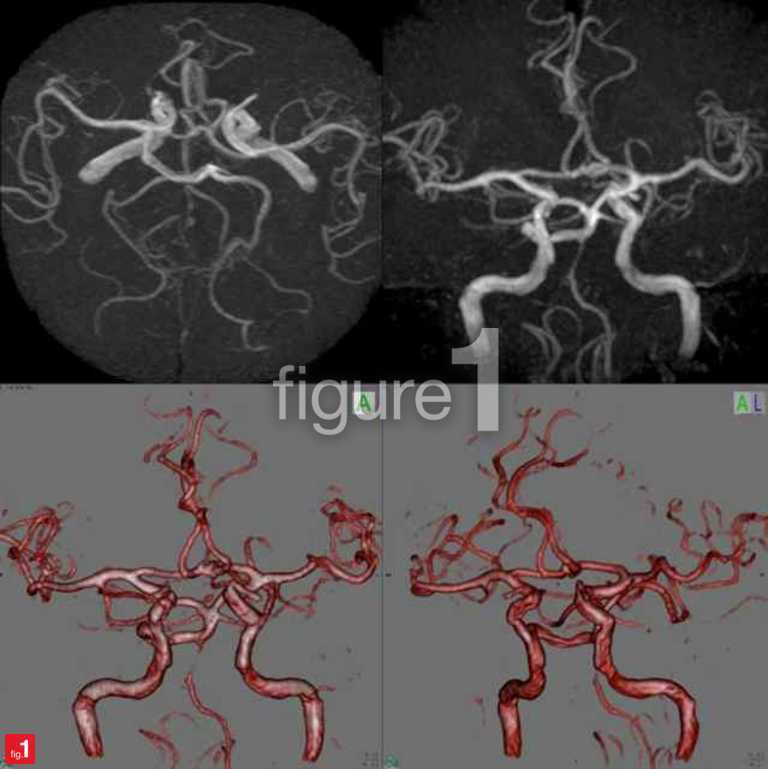

Figure 1

Figure 1, una nueva aplicación conocida como el ‘Instagram para médicos’, promete revolucionar la forma en la que los doctores buscan opiniones médicas sobre casos difíciles y únicos. No obstante, ya ha levantado suspicacias y dudas sobre el tratamiento que recibe en esta red social la privacidad de los pacientes.

Figure 1 permite a los profesionales médicos compartir fotos y comentarios de aquellos casos clínicos menos comunes e interesantes para la comunidad científica. El principal objetivo es el de proporcionar o buscar asesoramiento, opiniones médicas u opciones de tratamiento de las distintas enfermedades o dolencias.

De acuerdo con Figure 1, todas las imágenes publicadas son revisadas previamente con mucha cautela y precisión para eliminar toda la posible información personal que contengan, como es el caso de determinados detalles físicos que podrían identificar a los pacientes (caras, tatuajes, piercings, etc.). Se oscurecen o se eliminan utilizando las propias herramientas de edición que integra la aplicación.